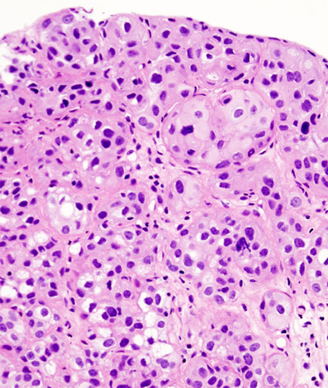

Bladder cancer is a complex neoplasm with multiple histologic subtypes and a wide spectrum of clinical states, ranging from relatively nonlethal Ta cancers to virulent M1 disease.